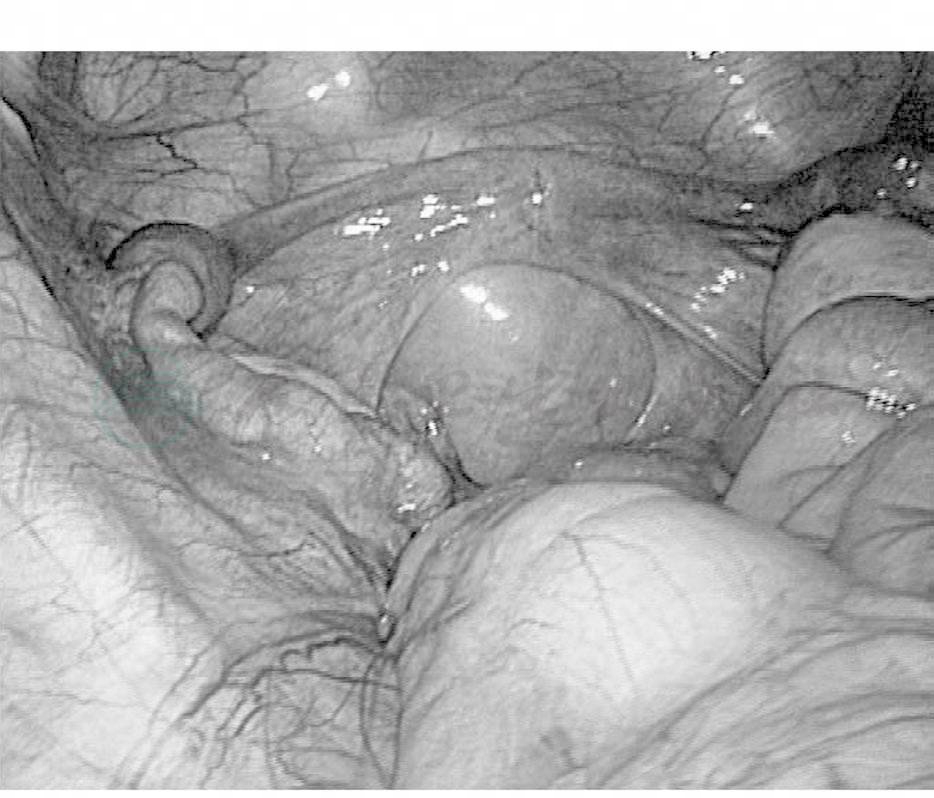

手术方式包括:①顶压法阴道成形术;②游离皮瓣阴道成形手术;③羊膜法阴道成形手术;④乙状结肠代阴道成形手术;⑤外阴阴道成形手术(Williams手术);⑥腹膜法阴道成形手术(经腹和经腹腔镜手术途径);⑦生物网片阴道成形手术。各种手术方式各有优缺点,目前没有一种定论,近年来经腹腔镜下行腹膜法阴道成形手术开展较多,该方法减少了开腹手术的创伤,使患者心理更易接受,手术步骤:以去甲肾上腺素1ml+生理盐水500ml配成的1∶500稀释液,于尿道与肛门之间作一水垫直至盆底腹膜,在膀胱与直肠之间首先进行人工阴道造穴,腹腔镜下以腹膜推进器下推盆底腹膜至会阴部,间断缝合腹膜与外阴造穴口,最后镜下沿始基子宫、侧腹膜、直肠及膀胱浆膜面荷包缝合,形成人工阴道顶端(图2、图3)。

图2 尿道与肛门之间作一水垫直至盆底腹膜

图3 腹膜阴道推进器下推腹膜